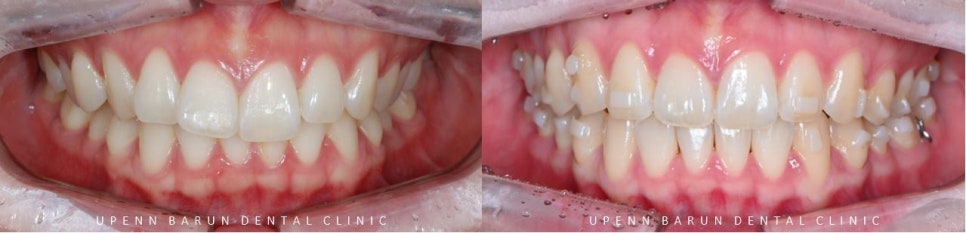

인비절라인라이트 케이스 (Invisalign Lite Case)

첫번째 클린체크 (14개 장치)

첫번째 14개 장치의 교정기간 23/4~23/8 (5개월)

잠실교정치과 유펜바른치과에서

인비절인라이트 옵션인 단 14개의 장치로

튀어나와 뻐드러져 있던 앞니의 각도가 개선이 되고

앞니들이 제 자리를 찾으며

삐뚤빼뚤했던 치아들이 올바르게 배열되었습니다.

두번째 클린체크 (14개 장치)

2nd clincheck

교정기간 23/4~24/3(11개월)

추가 14개의 장치를 통해

인비절라인교정치료가 잘 마무리 되었습니다 :)